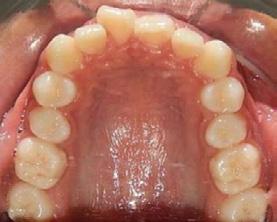

Figura 6. Oclusal superior e inferior de inicio.

presencia de hábito de interposición lingual (Figura 3), clase I molar derecha (Figura 4), clase I molar izquierda ( Figura 5 ), línea media facial y dental superior coinciden, línea media facial y dental superior desviada 1 mm a la derecha apiñamiento severo en la arcada superior (Figura 6) y en la arcada inferior.